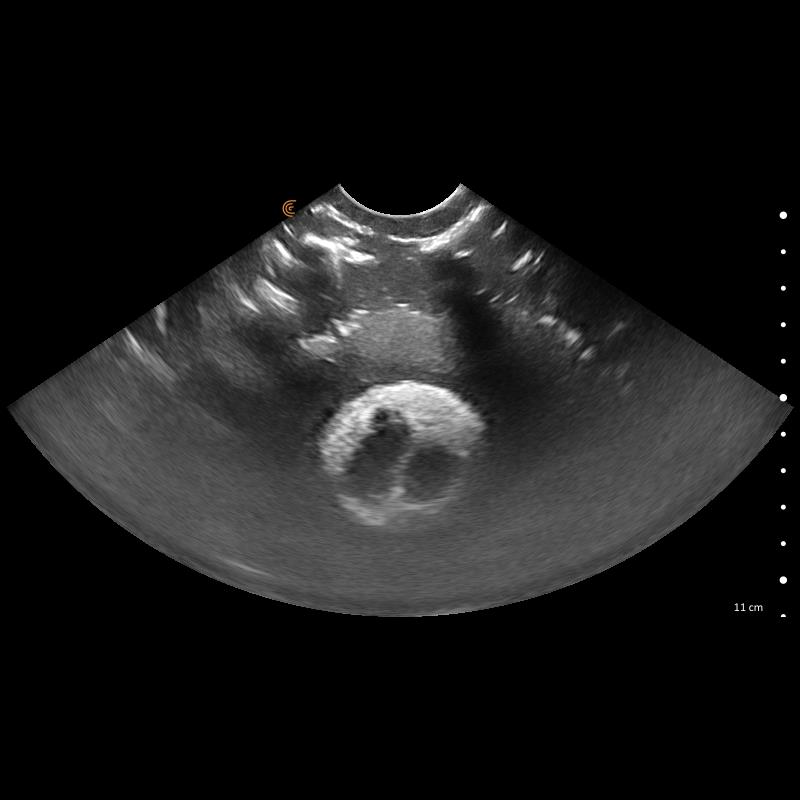

Le kit de formation fantôme à l’échographie canine "Lillie" Erler Zimmer est un outil indispensable pour la formation et la pratique en échographie vétérinaire. Conçu pour reproduire fidèlement l’anatomie canine, il permet aux professionnels de Santé vétérinaires, étudiants et praticiens expérimentés de s’entraîner de manière réaliste sur tous les organes majeurs : cœur, poumons, foie, pancréas, reins, intestins et système vasculaire.

Ce kit complet inclut le module “Skills”, qui enrichit l’apprentissage en proposant des structures anéchogènes, nodules hyperéchogènes et zones d’évaluation, idéales pour simuler des situations cliniques complexes. Le bloc FNA auto-réparant offre la possibilité de pratiquer des ponctions et gestes interventionnels en toute sécurité, garantissant un entraînement répétitif sans patient vivant.

Simulation complète des organes canins : cœur, poumons, foie, pancréas, reins, intestins, vessie et vaisseaux majeurs.

Module “Skills” avancé : nodules, structures anéchogènes et échogènes, vaisseaux spiraux pour un entraînement ciblé.